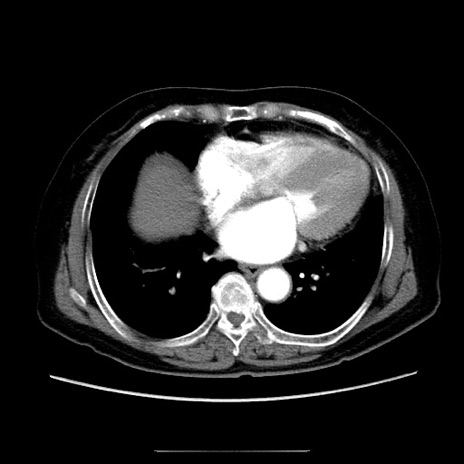

症例5(横断像)

【症例】70歳代女性

【主訴】お腹が張る

【現病歴】1週間くらい前から腹部膨満の自覚あり。昨日夜から増悪したため、本日救急外来受診。

【身体所見】意識清明、BT 36.5℃、BP 165/106mmHg、HR 80bpm、SpO2 98%、腹部:膨満、軟、自発痛・圧痛なし、触診にて不快感あり、腸蠕動音:減弱

【データ】WBC 12600、CRP 1.04